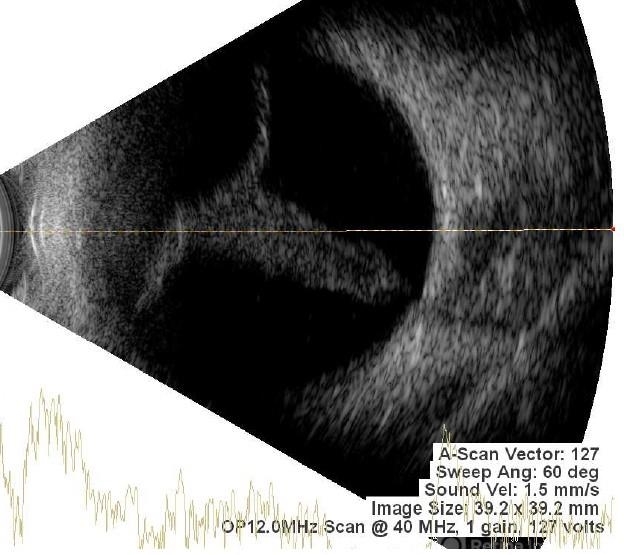

- B scan ultrasound, A-scan ultrasound, Closed funnel RD

- Membranous echoes with high spikes with restricted after movements suggestive of retinal detachment ( closed funnel configuration )